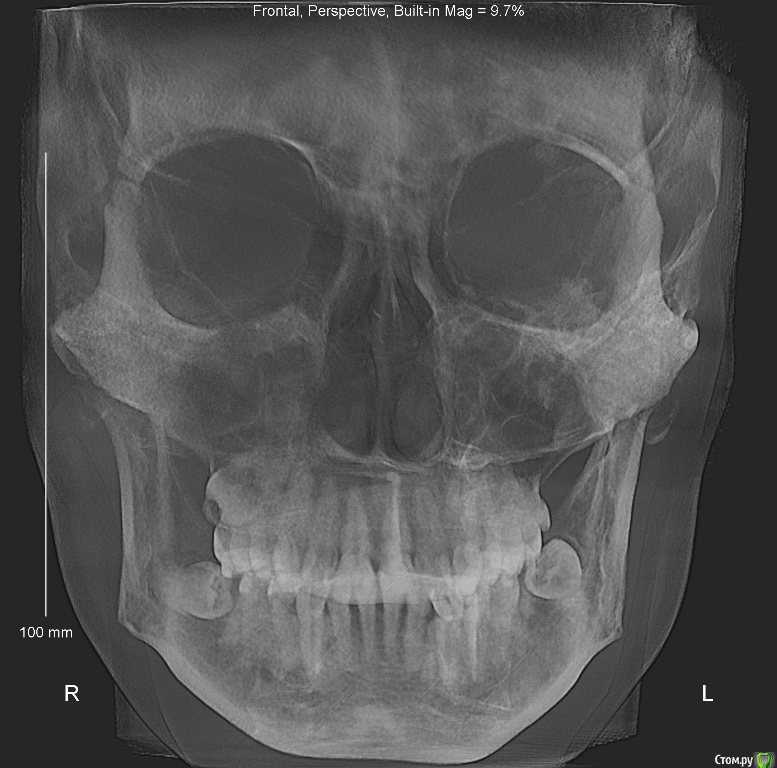

Dosya Опубликовано 12 апреля, 2018 Поделиться Опубликовано 12 апреля, 2018 Здравствуйте,в 1992 г - удалены две четверки сверху, носила пластинки около года. На нижней челюсти лечение не проводилось.в 2011 - 2012 году были удалены 2 четверки снизу, проведено ортодонтическое лечение: брекеты стояли только на нижней челюсти. В результате сформирован глубокий прикус, появилась рецессия десны на передних нижних зубах, стачиваемость зубов, дефект речи.В 2016 году обратилась к ортодонту с просьбой исправить прикус, чтобы иметь возможность нормально разговаривать. Доктор перенаправила меня к ортопедам для коррекции височно-челюстного сустава с помощью капы. Капу одеваю на ночь уже 2 года. Обещанного выдвижения челюсти и коррекции речи не произошло. Обратилась к ортодонтам повторно. Выбрала 4 ортодонтов по отзывам и получила 4 разных мнения:1. ничего не трогать, иначе, будет хуже.2. хирургическая коррекция - выдвижение нижней челюсти3. коррекция коронками высоты зубов (что не решает мою проблему с речью)и 1 доктор, все-таки, готов исправлять мой прикус брекетами Insignia после пластики десны.Мой вопрос: не выпадут ли передние нижние резцы при установке брекетов из-за недостатка костной ткани на нижней передней десне? Возможно ли в моем случае лечение без оперативного вмешательства? Ссылка на комментарий

Dosya Опубликовано 12 апреля, 2018 Автор Поделиться Опубликовано 12 апреля, 2018 Спасибо за ссылку. КТ загружены в предыдущем сообщении. Фото прилагаю. 1 Ссылка на комментарий